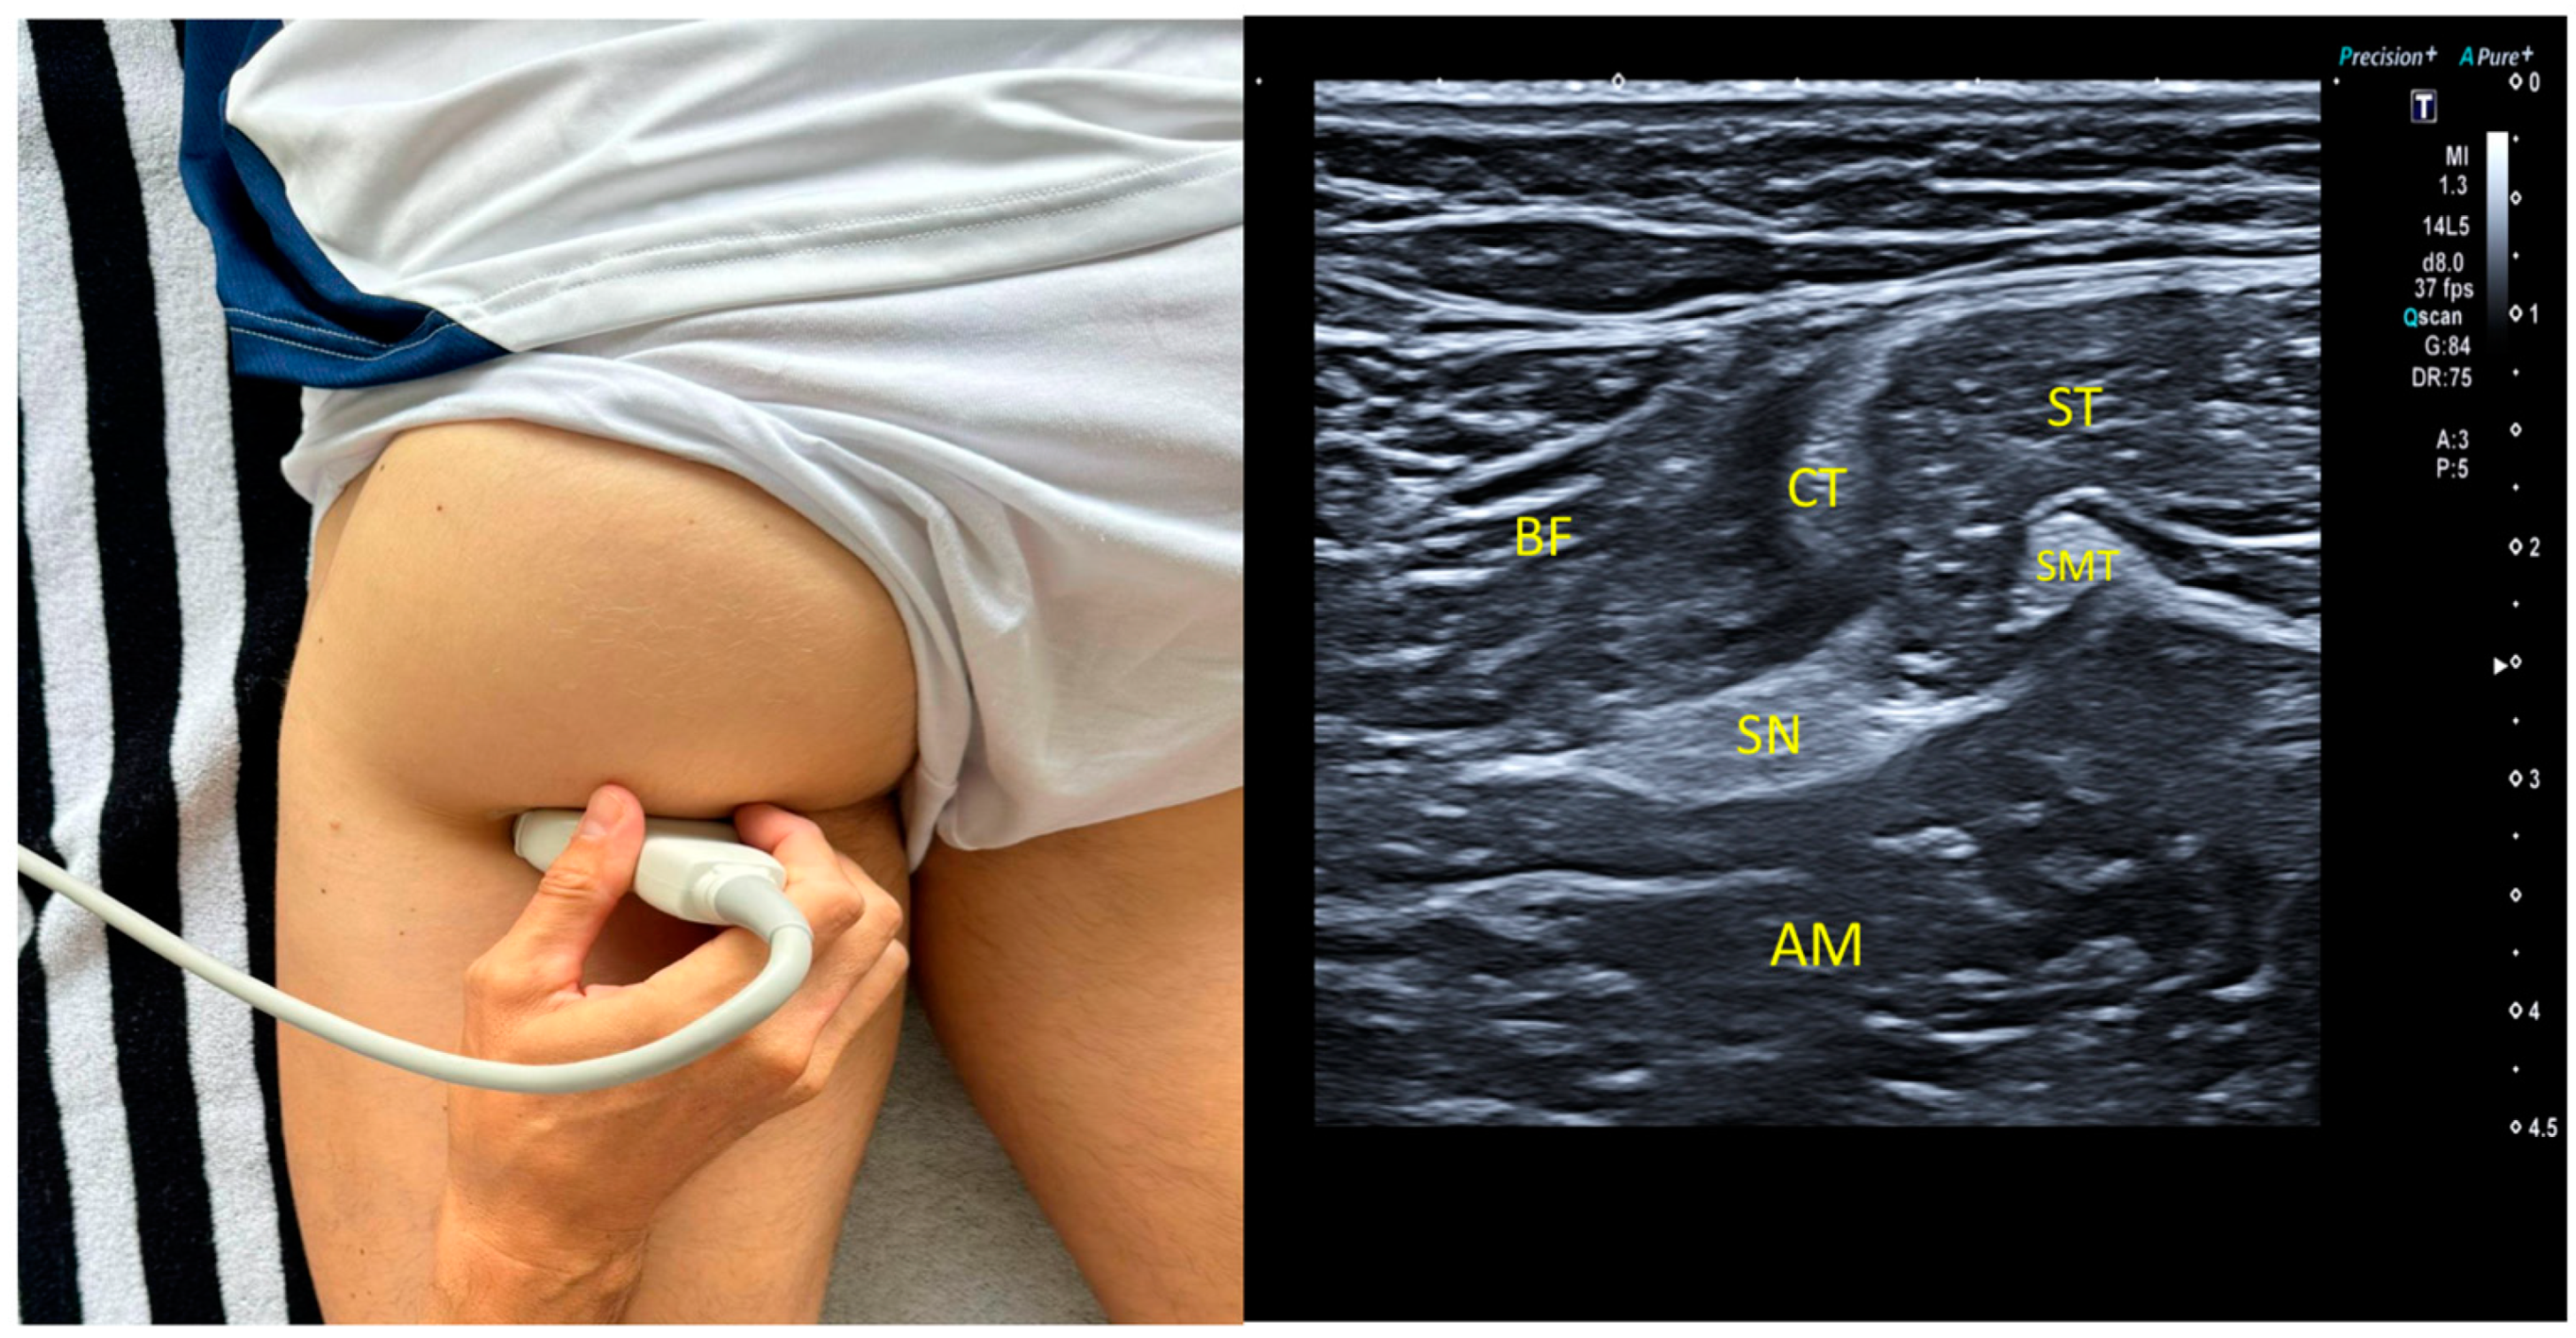

2.5. Ultrasound Imaging Procedure: Sciatic Nerve

2.6. Proximal Measurement1